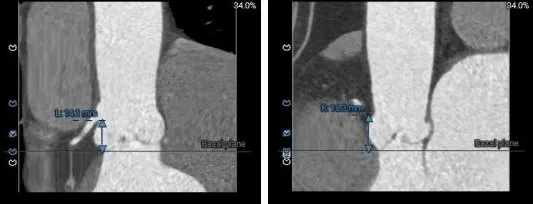

冠脉风险评估

LCA Height 14.1mm

RCA Height 16.3mm

LCA & Leaflet 14.9mm&11.6mm

RCA & Leaflet 13.7mm&12.7mm

瓣环水平夹角49度,非横位心

冠脉高度可,瓣叶不长,冠脉阻挡风险不高